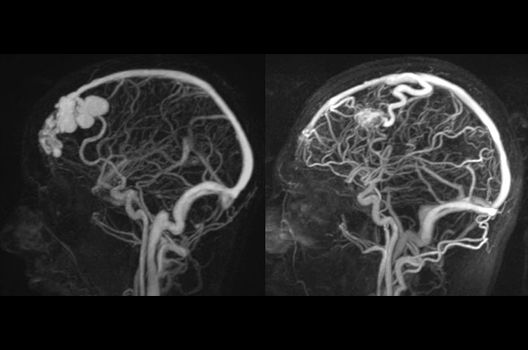

- Arterielle und venöse Angio-MRT

Die Magnetresonanztomographie (MRT) ist ein Verfahren, bei dem durch magnetische Kräfte Bilder des Körperinneren angefertigt werden. In der Neuroradiologie können manchmal kleinste Veränderungen schwere Folgen haben; daher forschen wir an der Entwicklung hochauflösender MRT-Sequenzen, mit denen diese Prozesse und auch einzelne Nervenfaserbahnen sichtbar gemacht werden können. Darüber hinaus sind bei vielen Erkrankungen des Gehirns die Blutgefäße betroffen. Daher arbeiten wir an der Neu- und Weiterentwicklung von MRT-Sequenzen zur Darstellung der Blutgefäße und zur Blutflussanalyse (sog. „Angio-MRT“). Einen besonderen Forschungsschwerpunkt unserer Klinik stellen die MR-Protonenspektroskopie und die funktionelle MRT dar, mit denen die Analyse einzelner chemischer Substanzen im Hirngewebe oder die Darstellung ausgewählter Hirnfunktionen möglich ist.

- Behandlung intrakranieller Gefäßmissbildungen

- Diagnostik und Therapie vaskulärer Anomalien (ZVA)